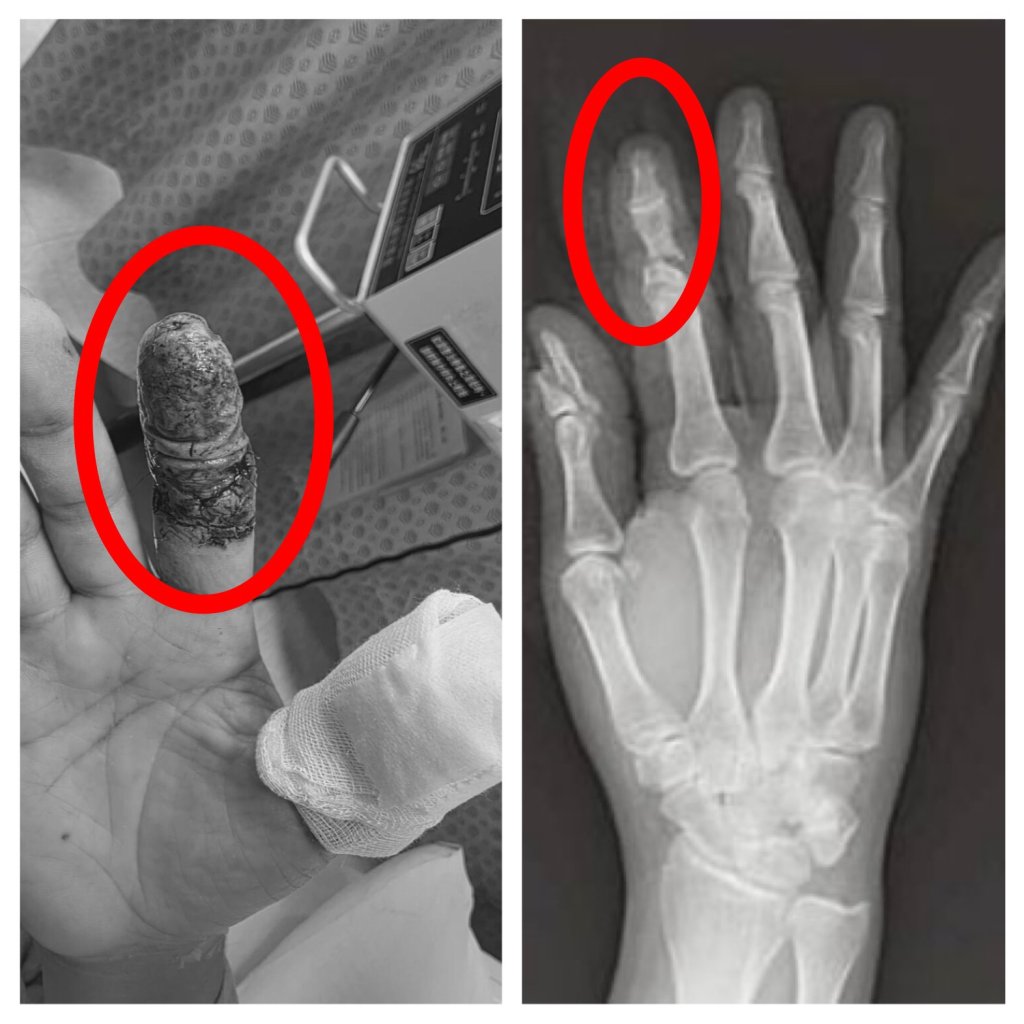

無人機削斷手指險截肢! 豐原醫院一個月「血流保衛戰」成功保住手指

豐原一名45歲林姓男子日前操作大型無人機時發生意外,高速旋轉的螺旋槳瞬間擊中右手,食指幾乎完全斷離,僅剩少量皮膚相連,傷勢嚴重,緊急送往衛生福利部豐原醫院救治,經外科醫師陳明澤評估屬重大手指創傷,若血流未恢復恐須截指,立即進行清創與重建手術,透過顯微技術接合受損血管與組織,成功建立循環,為後續組織存活爭取關鍵時間。患者住院期間長達一個月,最終順利出院,成功保住手指外觀與功能。-